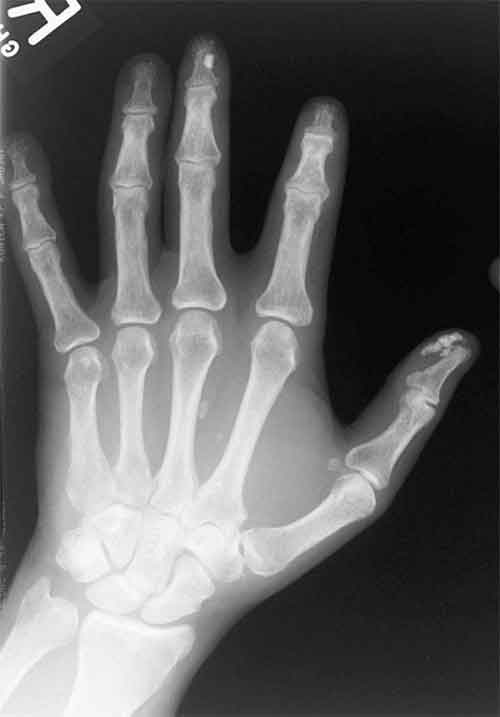

Per la prima volta dal 1980 lo scleroderma ha dei nuovi criteri di classificazione, che permetteranno di avere diagnosi piu’ precoci e trattamenti mirati.

A metterle a punto e’ stata una commissione congiunta di societa’ scientifiche europee e statunitensi, che li hanno pubblicati su ‘Arthritis and Rheumatism’. Lo scleroderma e’ una malattia rara del tessuto connettivo che determina un ispessimento di tutti i tessuti a causa dell’accumulo di collagene.

“C’era bisogno di una migliore classificazione – scrivono gli autori – perche’ i vecchi criteri non erano abbastanza sensibili per identificare i pazienti con la malattia allo stadio iniziale”. Ora ad esempio un ispessimento della pelle della parte mediale delle dita e’ sufficiente per una diagnosi. I criteri sono stati testati su veri pazienti, e la loro accuratezza e’ risultata del 90 per cento rispetto al 75 di quelli precedenti.